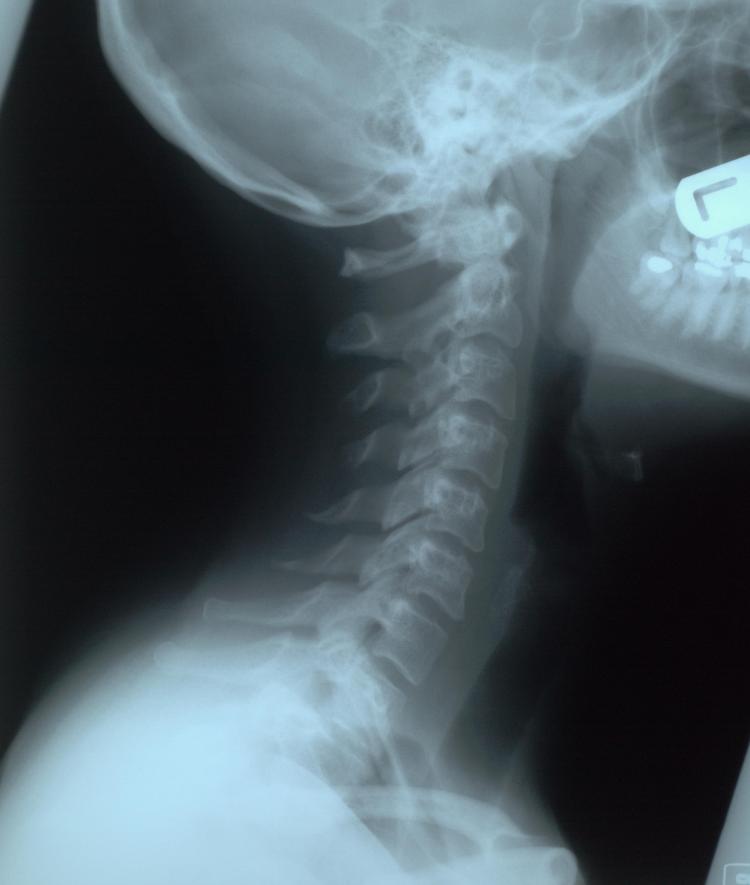

Tomogramas: este tipo especial de rayos X borra todas las capas de los dientes, excepto la exacta que el dentista necesita para identificar un problema específico. Proyecciones cefalométricas: utilizadas principalmente por los ortodoncistas, estos proyectos examinan el lado de la cabeza y cómo se colocan los dientes en relación con la mandíbula y el perfil. Sialografía: un dentista que busca problemas con las glándulas salivales (como obstrucciones de las glándulas salivales o el síndrome de Sjögren) puede usar este tipo particular de rayos X usando un medio de contraste. Tomografía computarizada: las tomografías computarizadas no son necesariamente comunes en un consultorio dental, pero se pueden usar en el hospital, se usan con mayor frecuencia para ver la ubicación de los huesos y problemas con los huesos faciales (como fracturas). Es posible que necesite una tomografía computarizada si necesita una cirugía oral compleja. Tomografía computarizada de haz cónico: CBCT para abreviar, este nuevo desarrollo en tecnología dental a veces se denomina radiografía 3D. Esto puede ayudar a revelar lesiones que de otro modo estarían ocultas en las radiografías 2D, razón por la cual se utiliza para que los pacientes de endodoncia identifiquen los procedimientos fallidos.